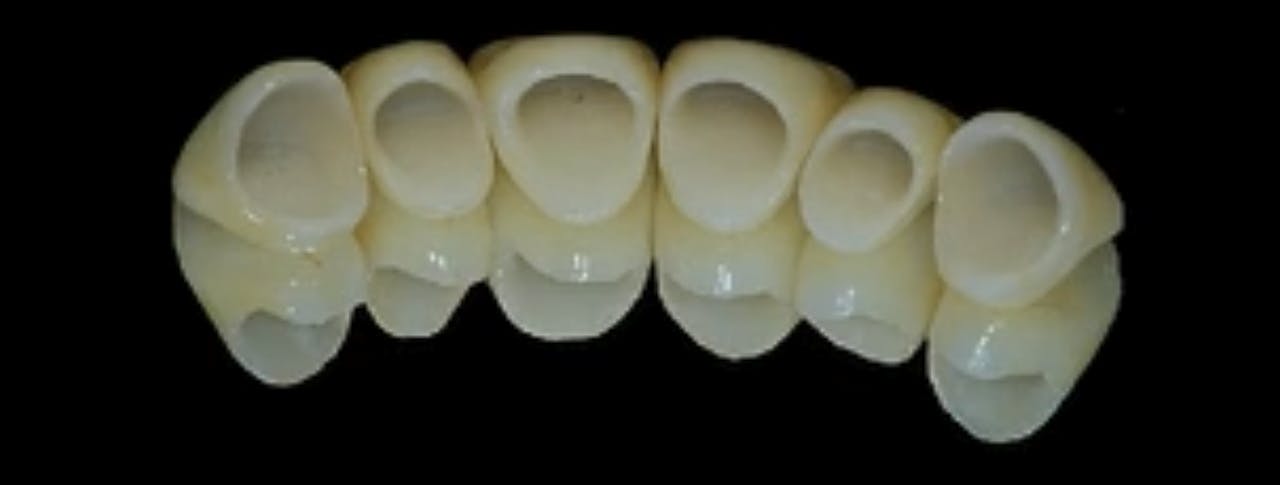

AllCeramic Solutions On Teeth & Implants gIDE Dental Institute Gide Dental Reviews • 550+ clinical videos on web and app • new dental videos added. Clinical videos, expert interviews, live broadcasts over. Evidence based video education at its best. Premiere provider of online dental education. Learn from the world's most trusted faculty and advance your skills with gide. Gide dental | 280 followers on linkedin. 31,762 likes · 74 talking about this. Gide Dental Reviews.